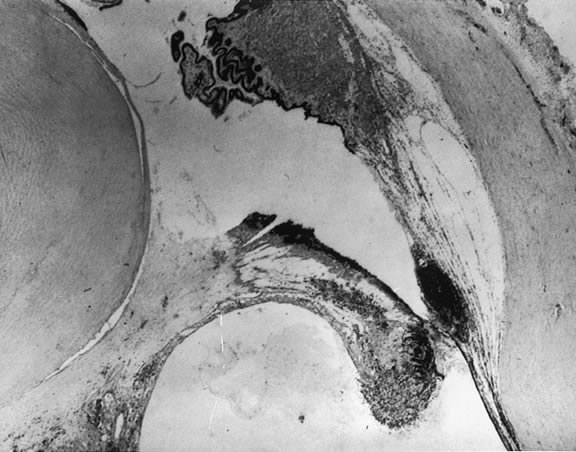

The nature of the adhesion between the vitreous cortex and the ILM is enigmatic. This adhesion is strongest at the optic nerve, the macula, the vitreous base, and retinal vessels. Foos6 demonstrated attachment plaques between Müller's cell cytoplasm and the ILM in the basal and equatorial retina (Fig. 2). Vitreous traction mediated by vitreous fibrils may contribute to these adhesions. These attachment plaques are not present posterior to the equator except where the ILM is thinned in the fovea. This anatomic variation in the fovea region may play a role in the pathogenesis of some of the vitreomacular disorders.

Fig. 2. Electron micrograph of the vitreoretinal junction (J) 1 mm posterior to the equator of the eye. This demonstrates the insertion of the vitreous fibers to the inner limiting lamina (L). Attachment plaques (P), which anchor the inner limiting lamina to the surface glial cells, are illustrated. (Foos RY: Anatomic and pathologic aspects of the vitreous body. Trans Am Acad Ophthalmol Otolaryngol 1973;77:171)